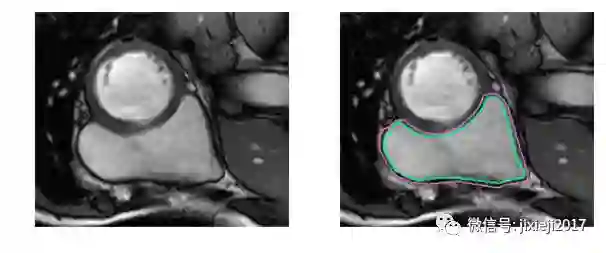

不使用医学术语,识别右心室困难的原因是:左心室是一个厚壁的圆柱型区域,而右心室是一个不规则形状的物体,较薄的心室壁有时会与周围的组织混在一起。下图是MRI快照中手工绘制的右心室内壁和外壁(心内膜和心外膜)轮廓:

上图的分割较简单。下面是一个比较困难的分割: